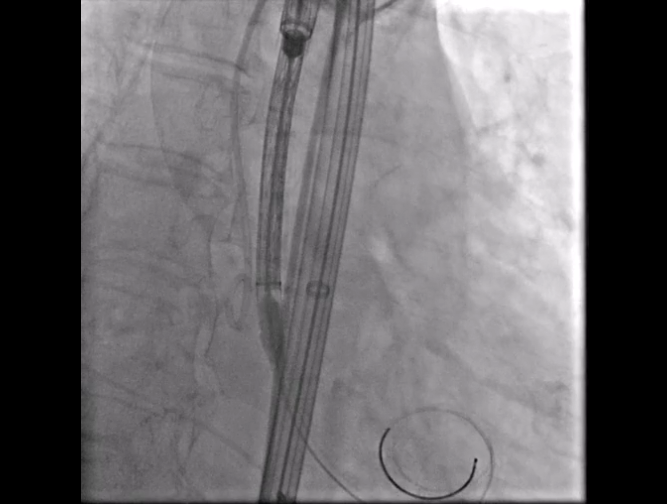

Step 2.建立大鞘通路:大鞘通过升主、边进入边加弯,避免剐蹭弓部斑块

手术中其实有个关键点,在可调弯鞘过弓的时候,我们特意放慢了速度,一遍进一遍调弯,确保每一步都不触碰弓顶钙化。这台手术的成功,本质上是 “病变特点和器械特性” 的精准匹配。对同类型来说,碰到瓷化升主动脉合并复杂弓的病例,建议术前一定要把钙化范围、弓部角度这些解剖细节分析透,器械选择上不用局限于单一方案,多考虑协同作用,或许能找到更安全的路径。毕竟对我们来说,每台复杂手术的目标都一样:在保证安全的前提下,给患者带来最好的长期获益。